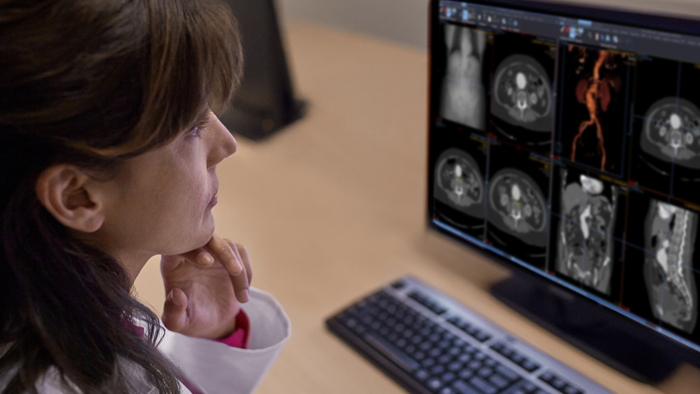

Image and data interpretation

AI-driven platforms for workflow orchestration, data access, advanced analysis, reporting and clinical collaboration.